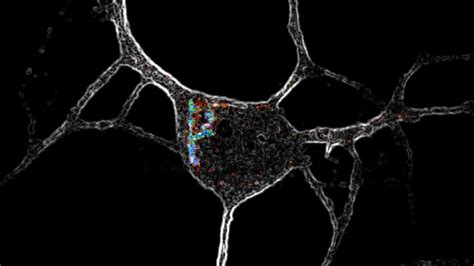

So, how exactly do psychedelics work their magic on the brain? It’s pretty mind-blowing stuff, guys! These compounds primarily interact with the serotonin system , particularly the 5-HT2A receptors. Serotonin is a neurotransmitter that plays a crucial role in mood, perception, and cognition. When psychedelics bind to these receptors, they essentially rewire neural pathways, leading to a temporary state of increased brain connectivity and a decrease in activity in areas like the default mode network (DMN). The DMN is often associated with self-referential thought and rumination, so dampening its activity can lead to a sense of ego dissolution and a more open, less critical state of mind. This interconnectedness allows different parts of the brain to communicate in novel ways, which is thought to be the basis for the altered perceptions, heightened emotions, and profound insights people experience. Imagine your brain as a network of roads , and usually, traffic follows the same well-trodden paths. Psychedelics, in a way, open up new routes and connections, allowing for different kinds of traffic to flow. This can lead to synesthesia (where senses get mixed, like seeing sounds), a distortion of time, and a feeling of being more connected to the universe. The intensity and nature of the experience can vary greatly depending on the substance, dosage, individual mindset, and setting. It’s this intricate dance between the drug and our neurochemistry that creates the unique tapestry of a psychedelic journey. Understanding these mechanisms is key to appreciating both the therapeutic potential and the inherent power of these substances. This scientific exploration is shedding new light on how consciousness itself works, moving beyond simple chemical reactions to embrace the complex interplay of our minds and the external world. We’re learning that these substances don’t just change our perception; they fundamentally alter the way our brains process information and construct reality, offering a unique window into the nature of our own awareness.